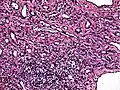

| Micrograph of a kaposiform hemangioendothelioma with "glomeruloid" nodules of endothelial cells. | |

- Kaposiform hemangioendothelioma (also known as "Infantile kaposiform hemangioendothelioma"[3]) is an uncommon vascular tumor, first described by Niedt, Greco, et al. (Hemangioma with Kaposi's sarcoma-like features: report of two cases.(Niedt GW, Greco MA, Wieczorek R, Blanc WA, Knowles DM 2nd. that affects infants and young children, with rare cases having also been reported in adults. Pediatr Pathol. 1989;9(5):567-75.)[2]: 596 [3]: 1782